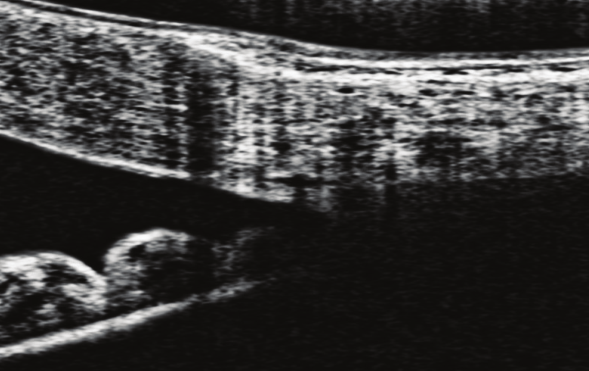

• Interplay between intraocular and intracranial pressure effects on the optic nerve head in vivo

• Z Zhu, S Waxman, B Wang, J Wallace, SE Schmitt, E Tyler-Kabara, H Ishikawa, JS Schuman, MA Smith, G Wollstein, IA Sigal

• Experimental eye research, 213, 108809, December 2021.

image